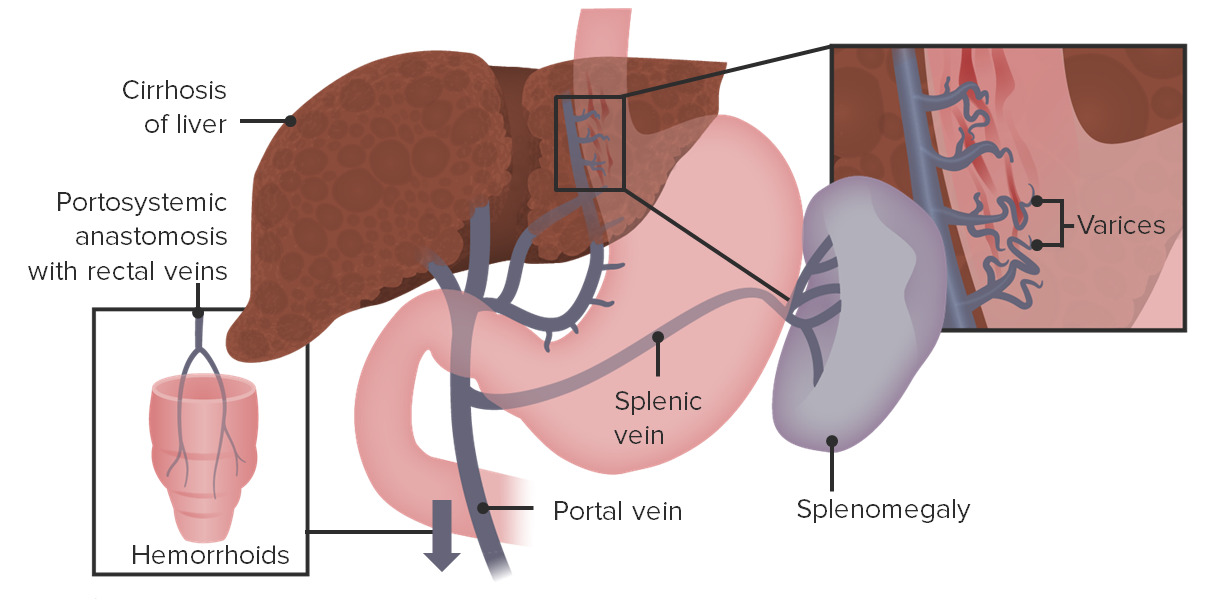

Why Does Portal Hypertension Cause Esophageal Varices Student Doctor

https://4.bp.blogspot.com/-zyELTH6YizU/T5YEaYLyi-I/AAAAAAAAADk/-oQ86Bh8P-c/s1600/esophageal+PPT+08+200ppi.tif

Portal Hypertension Interventional Radiology UCLA Health

https://www.uclahealth.org/sites/default/files/styles/max_width_027000_1080/public/images/portal-hypertension.png?itok=kYLRgHtF